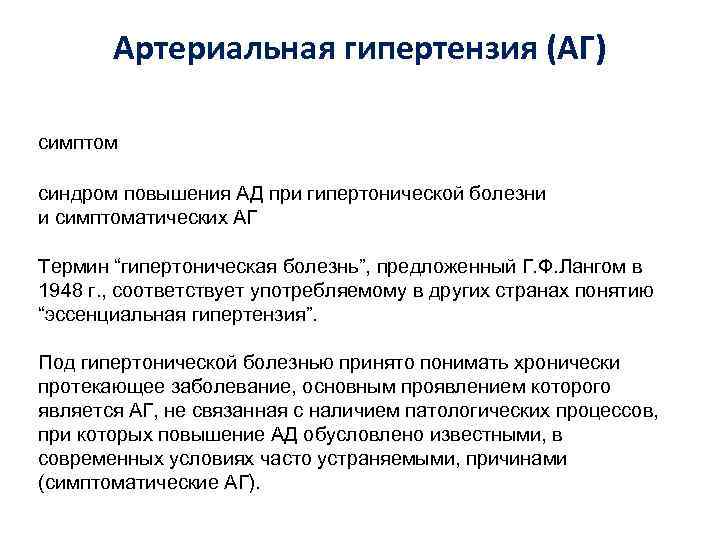

Артериальная гипертензия (АГ) симптом синдром повышения АД при гипертонической болезни и симптоматических АГ Термин “гипертоническая болезнь”, предложенный Г. Ф. Лангом в 1948 г. , соответствует употребляемому в других странах понятию “эссенциальная гипертензия”. Под гипертонической болезнью принято понимать хронически протекающее заболевание, основным проявлением которого является АГ, не связанная с наличием патологических процессов, при которых повышение АД обусловлено известными, в современных условиях часто устраняемыми, причинами (симптоматические АГ).

Артериальная гипертензия (АГ) симптом синдром повышения АД при гипертонической болезни и симптоматических АГ Термин “гипертоническая болезнь”, предложенный Г. Ф. Лангом в 1948 г. , соответствует употребляемому в других странах понятию “эссенциальная гипертензия”. Под гипертонической болезнью принято понимать хронически протекающее заболевание, основным проявлением которого является АГ, не связанная с наличием патологических процессов, при которых повышение АД обусловлено известными, в современных условиях часто устраняемыми, причинами (симптоматические АГ).